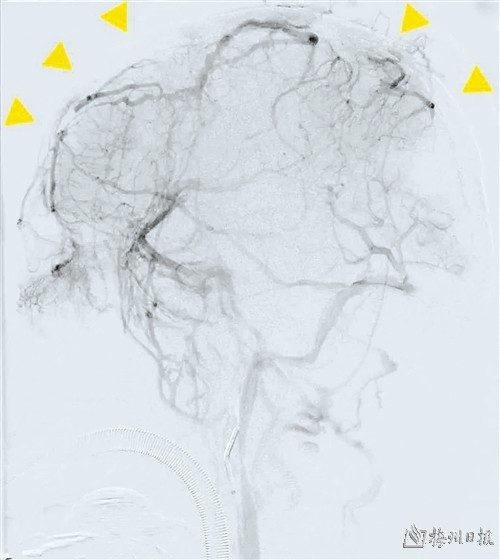

术前造影显示矢状窦不显影(黄色箭头指示闭塞的矢状窦)

近日,中山大学附属第三医院粤东医院(以下简称“粤东医院”)神经外科收治一位“突发头晕、头痛伴发作性意识障碍”的男性患者。入院时神志躁动,答不对题,查体不配合,CTA+CTP检查提示左额叶高密度影,考虑出血。因患者入院2周前有明显头晕、头痛症状,伴烦躁不安、寡言少语、精神疲乏症状,为了解颅内血管情况,于入院当天即进行全麻下脑血管造影检查。术中发现患者矢状窦、左侧横窦、左侧乙状窦未见显影,考虑静脉窦血栓形成。

在明确诊断后,征得患者家属的同意,粤东医院神经外科团队即刻给患者行静脉窦血栓取栓术。经多次取栓后,复查造影提示矢状窦、左侧横窦、左侧乙状窦重新显影,复通成功。术后复查头颅CT提示左额叶出血无增加。术后予适当脱水降颅压、积极抗凝、抗血小板聚集、维持内环境稳定等积极治疗。患者头晕、头痛症状较术前明显缓解,生命体征平稳,恢复顺利。